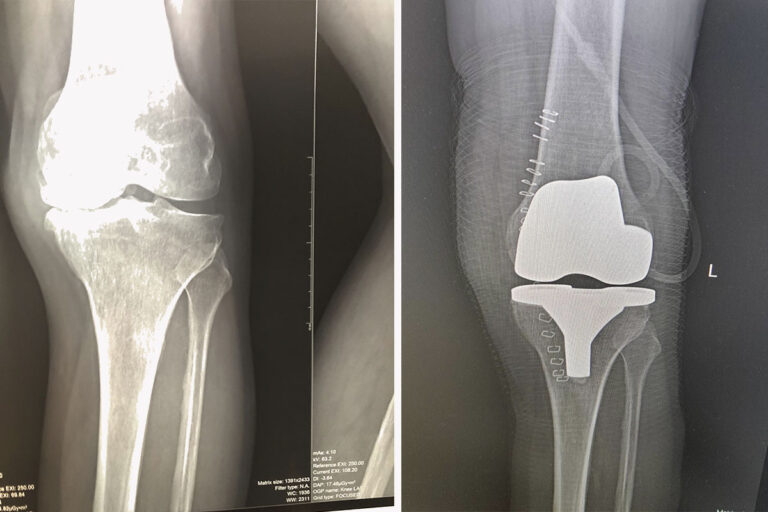

Виды протезирования коленного сустава

Эндопротезирование коленного сустава – полноценная хирургическая операция, в ходе которой пациенту меняют износившиеся или деформированные…